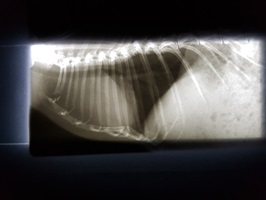

Ein Kaninchen mit Atembeschwerden oder den beschriebenen Augenveränderungen sollte zunächst geröngt werden. Hierdurch lassen sich Verschattungen im Brustkorb schnell und einfach erkennen und es muss anschließend nur noch ermittelt werden, ob es sich dabei um einen Tumor oder eine (reine) Herzerkrankung handelt. Letztere kann zu einem vergrößerten Herzen oder einem Erguss führen, was per Röntgendiagnostik nicht immer von einem Tumor zu unterscheiden ist.

Besteht eine entsprechende Verschattung, ist ein Herzultraschall angezeigt. Dabei können das Gewebe und die Herzfunktion eindeutig beurteilt werden. Dies ist auch deshalb von Bedeutung, da die Herzfunktion durch einen benachbarten Tumor beeinträchtigt werden kann. In diesem Fall muss das sekundäre Herzproblem in die Tumortherapie miteinbezogen werden.